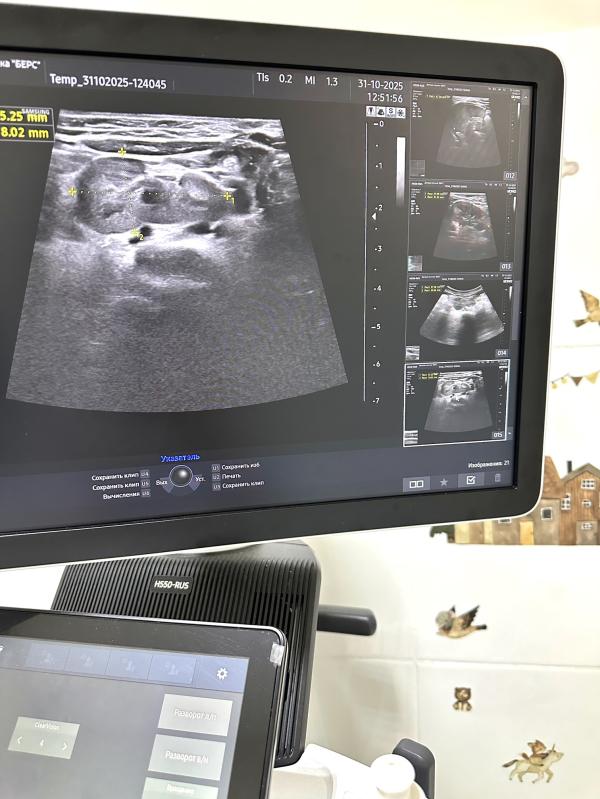

Решив детально разобраться, я провела расширенное ультразвуковое исследование. И почка нашлась! Просто оказалась не на своём привычном месте, а развернута и немного сдвинута вглубь тела, поближе к спинке малыша. Такое состояние называется поясничная дистопия почки.

А на уз-снимке у нас наша почка-потеряшка:)